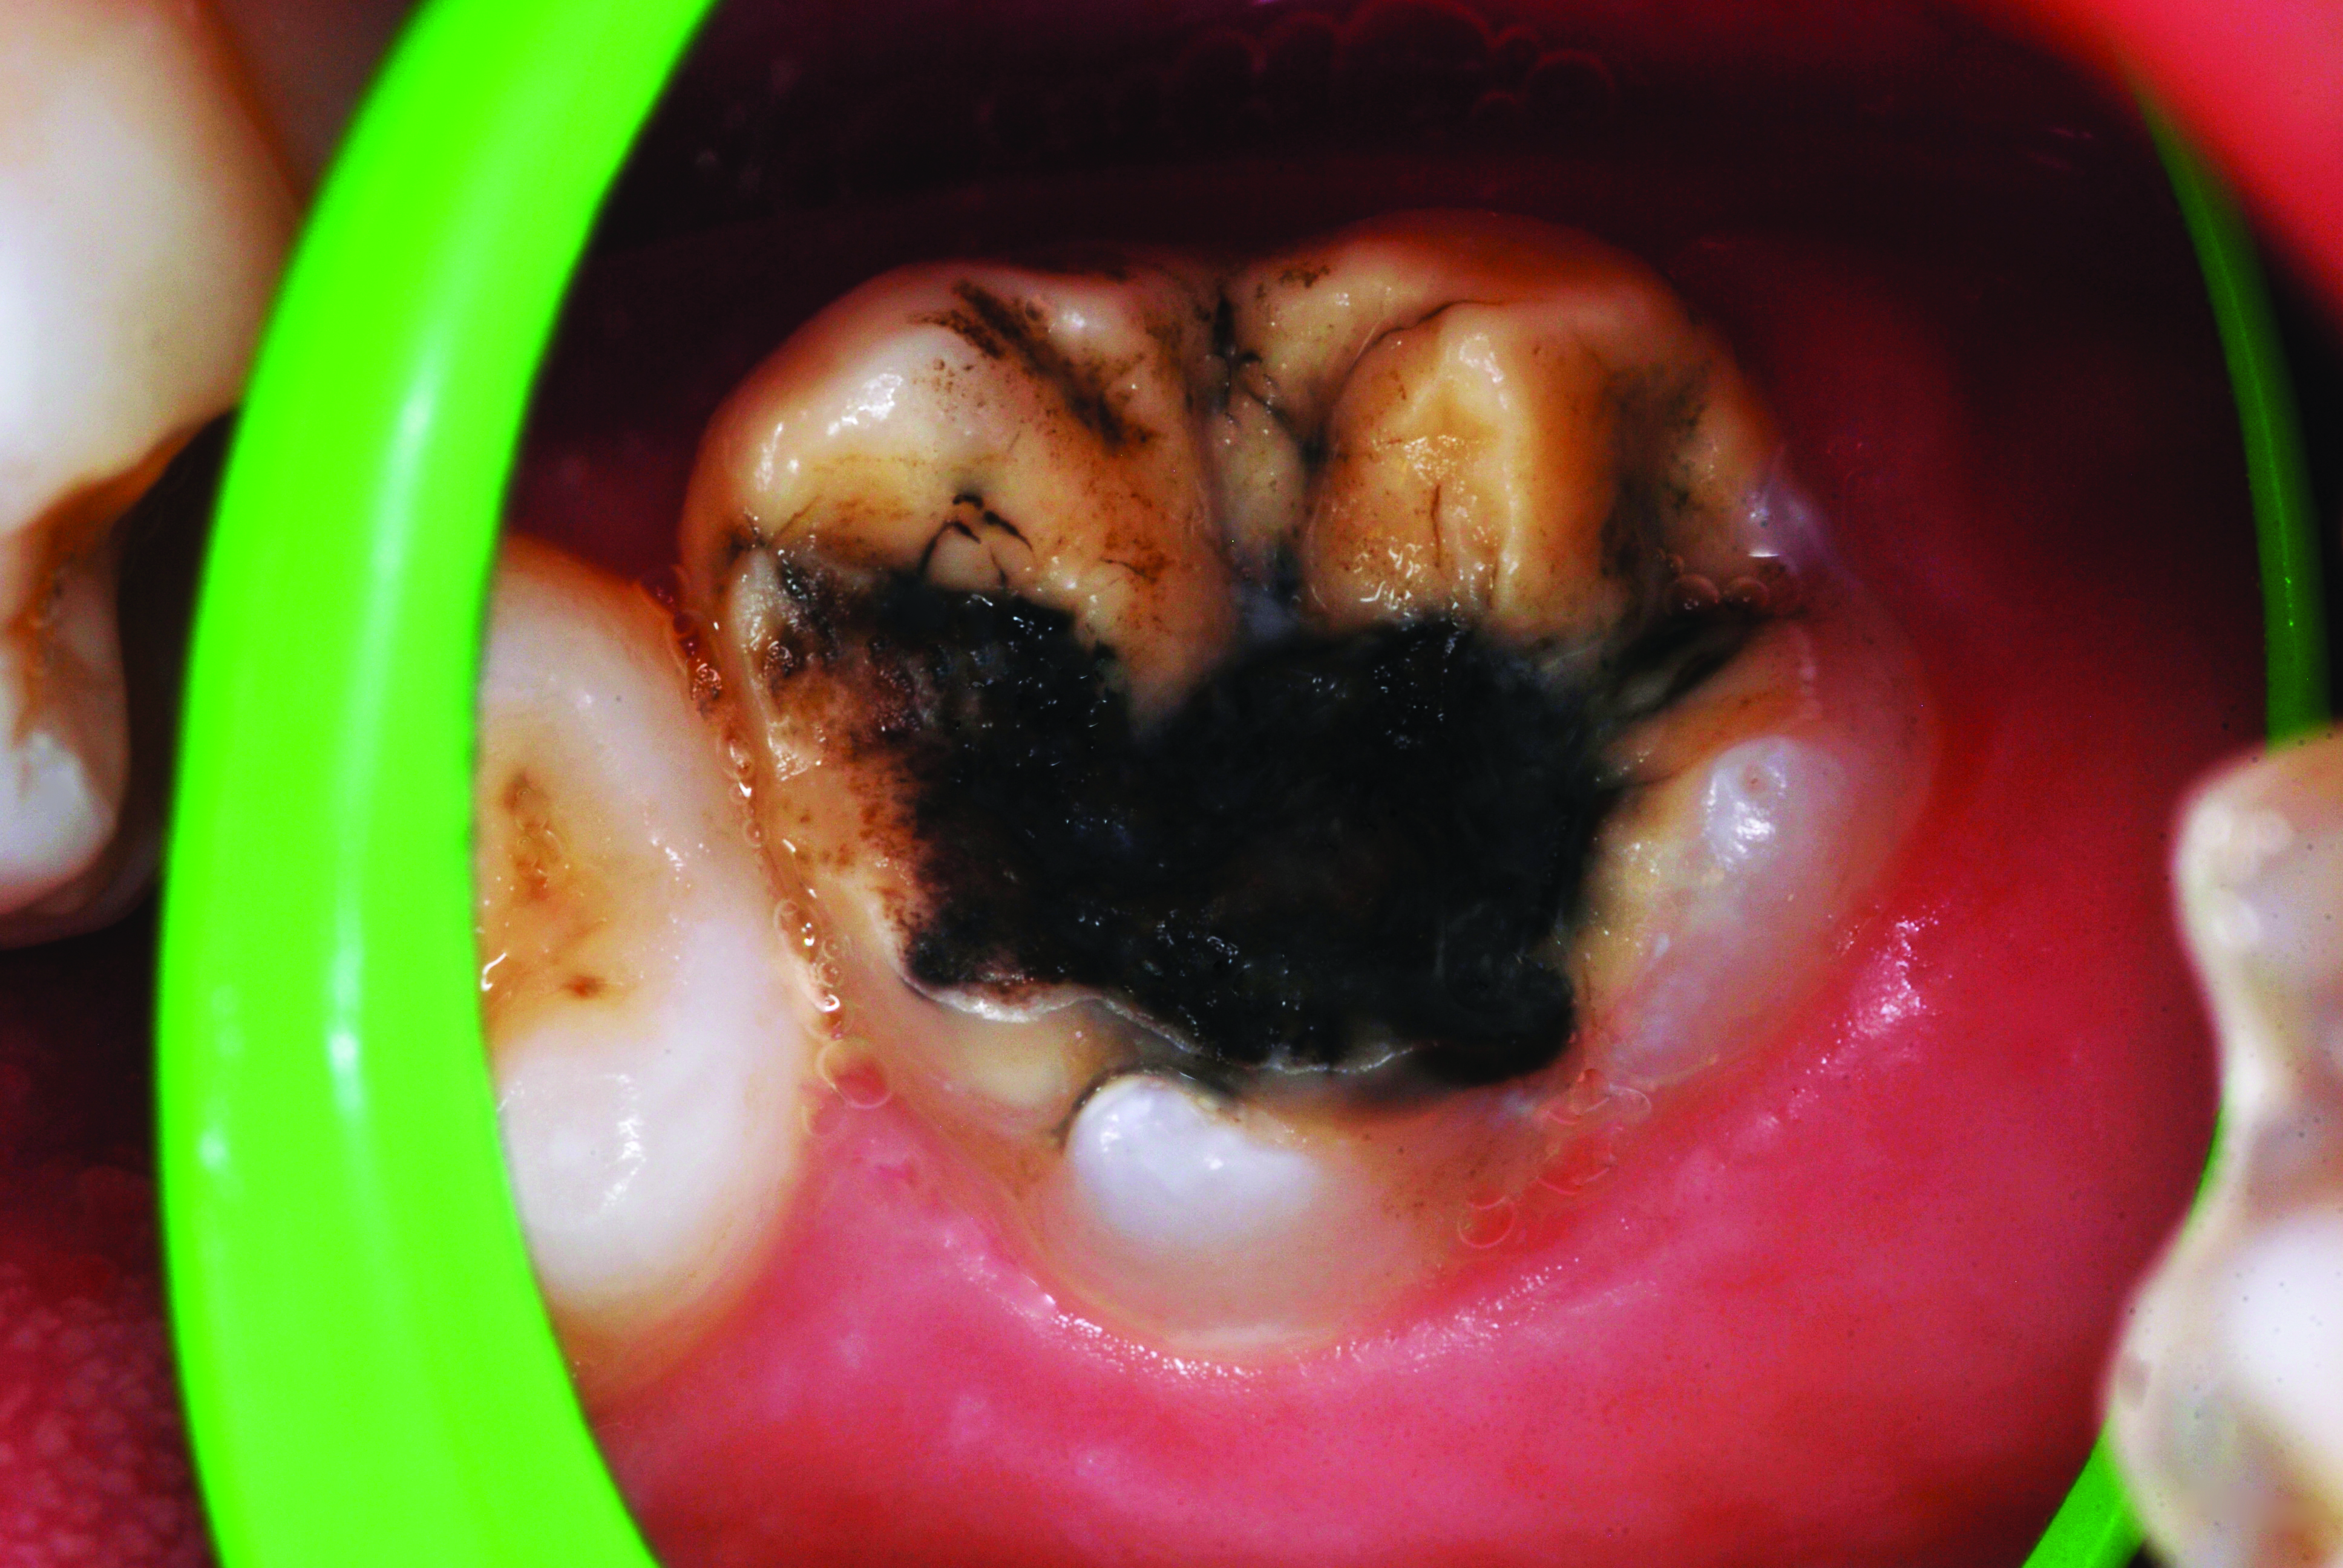

(2.) Lingual and facial maxillary views of 5-year-old patient, 1 year after caries attenuation with SDF. The parents were not concerned about the black staining.

Figure 2

(3.) Lingual and facial maxillary views of 5-year-old patient, 1 year after caries attenuation with SDF. The parents were not concerned about the black staining.

Figure 3